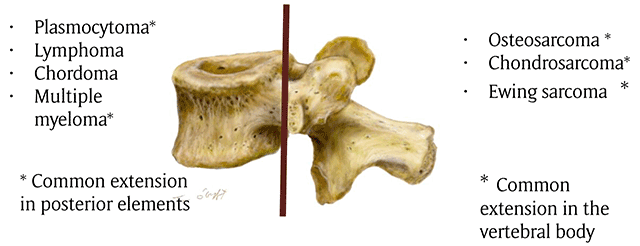

Figure 1

Drawing showing the common distribution of primary malignant tumors of spine. The brown line indicates the border between the vertebral body and posterior elements.